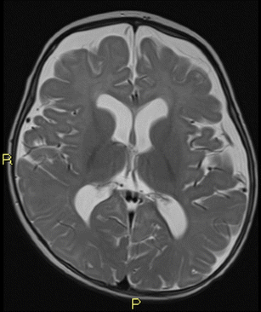

Fig. 2

Fig. 3